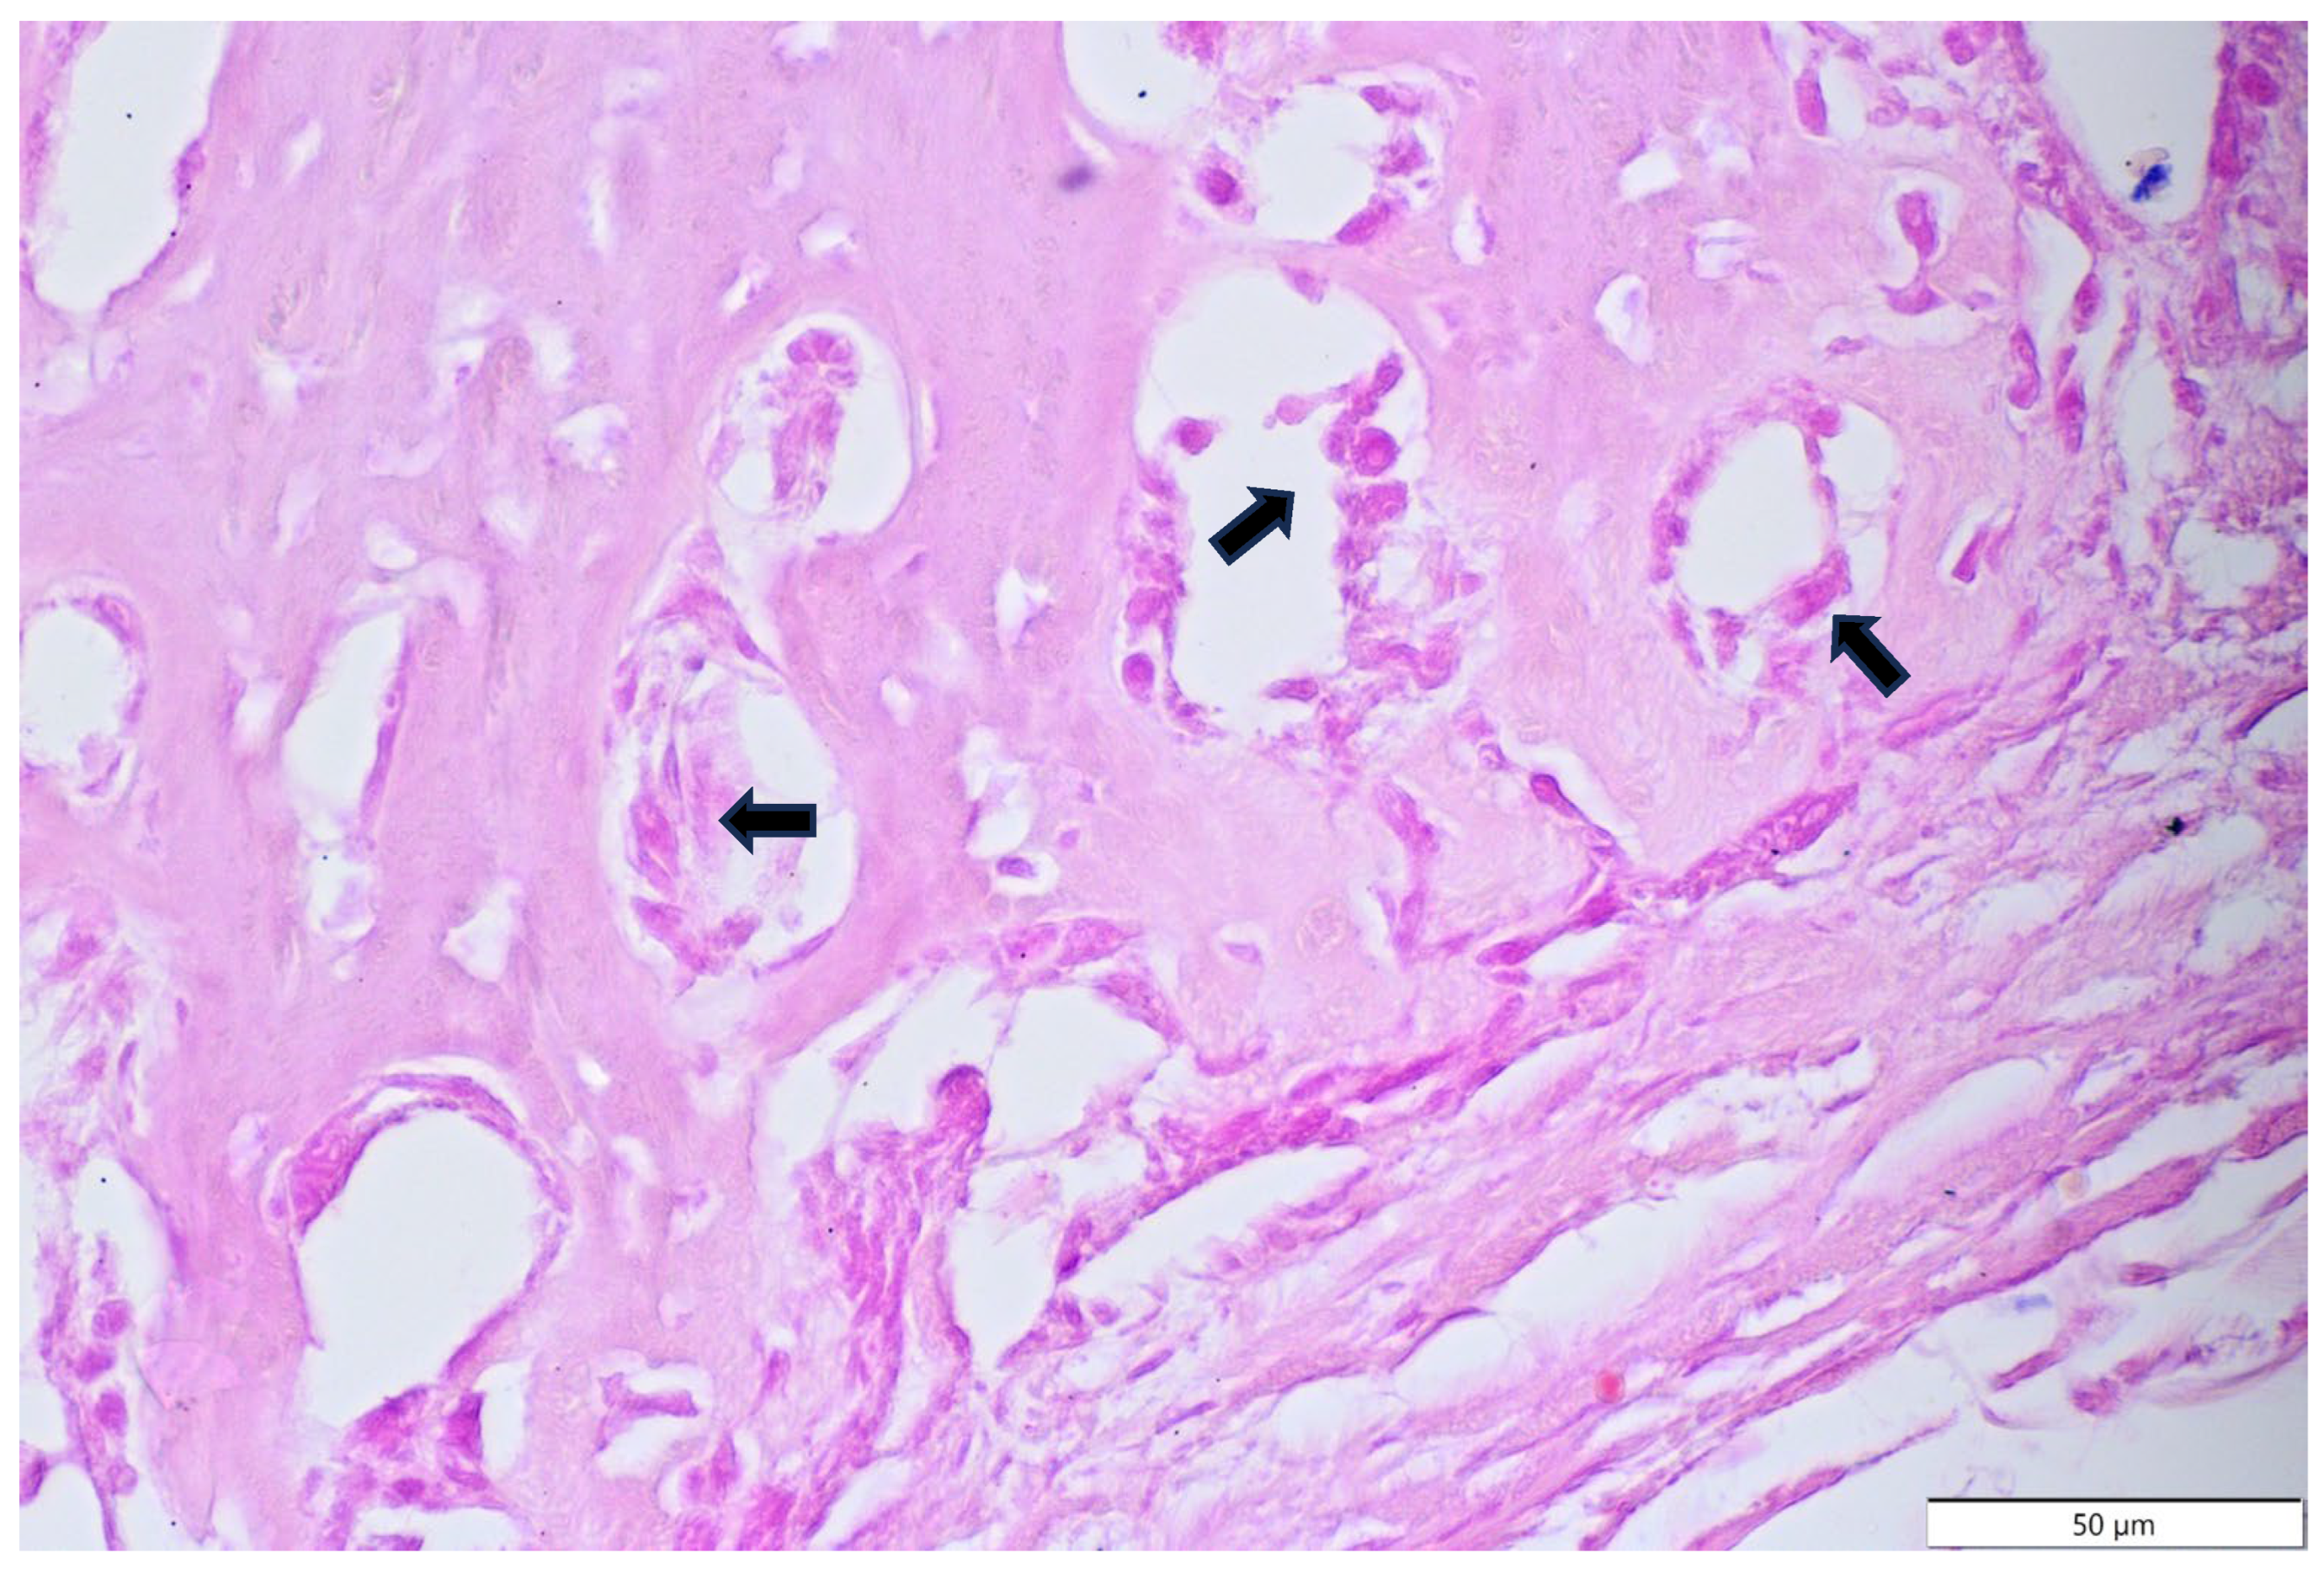

3.3. Results of Microscopic Examination